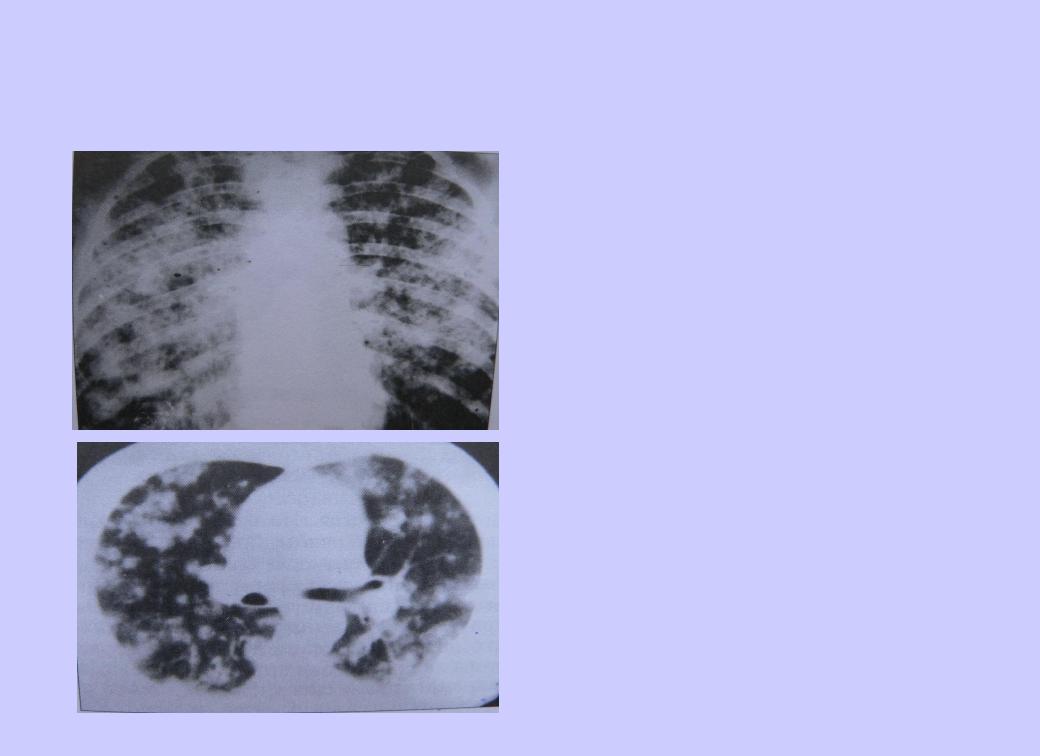

Иллюстрации по теме очагового и инфильтративного туберкулеза